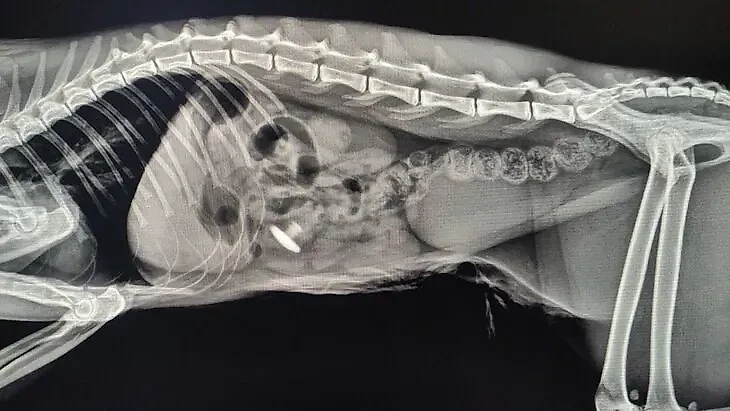

Кот Стёпа попал в Бутовскую ветклинику с рвотой и слабостью. При рентгене внутри него заметили заглушку для мебели. Ему сделали операцию и удалили инородный предмет, после чего котику полегчало, сообщили в столичной госветслужбе.

Заглушка от мебели внутри кота Стёпы. Обложка © ГБУ "Мосветобъединение"